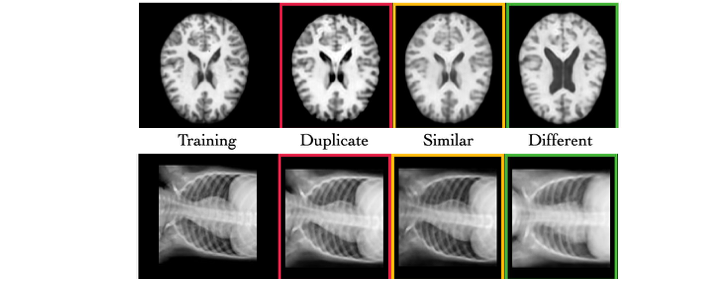

- Validato su immagini sintetiche MRI generate da un Latent Diffusion Model allenato in condizioni ad alto rischio di memorizzazione.